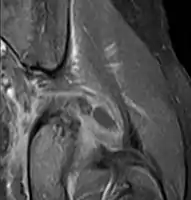

| Transverse T2 magnetic resonance imaging section through the hip region showing abscess collection in a patient with pyomyositis. | |

| Diagnostic method | Diagnostic method used for PM includes ultrasound, CT scan and MRI. Ultrasound can be helpful in showing muscular heterogeneity or a purulent collection but it is not useful during the first stage of the disease. CT scan can confirm the diagnosis before abscesses occur with enlargement of the involved muscles and hypodensity when abscess is present, terogenous attenuation and fluid collection with rim enhancement can be found. MRI is useful to assess PM and determine its localization and extension |